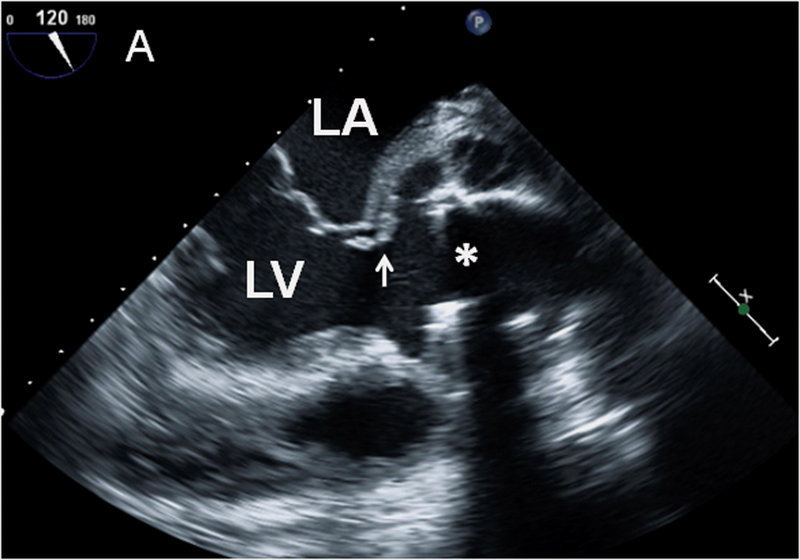

فحوصات تشخيصية لبعض امراض القلب والشرايين التاجية